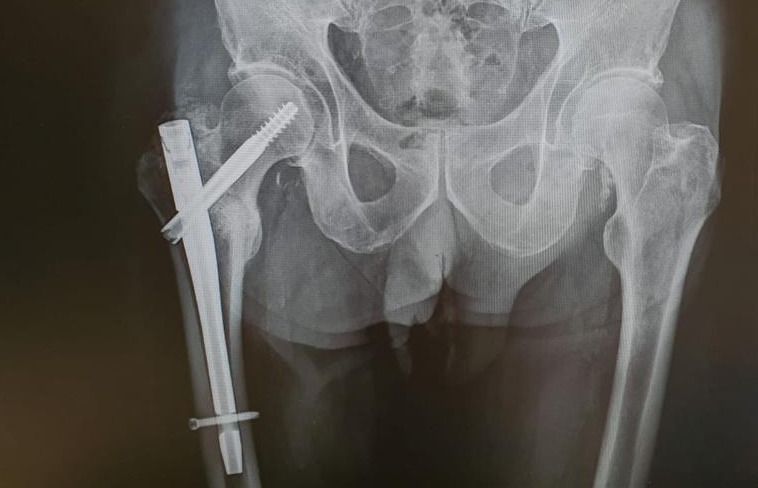

Radiografia de l'operació d'en Manel arran de l'atropellament d'un patinet elèctric. FOTO: Cedida

Successos

Un cerdanyolenc busca la persona que el va atropellar amb un patinet elèctric